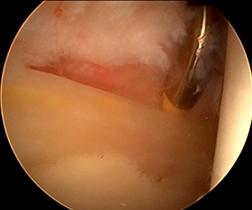

髋臼盂唇损伤的治疗方法包括保守治疗和手术治疗。保守治疗主要适应于症状较轻者,采取4周的卧床休息,逐渐进行肌力、本体感觉和负重练习,必要时可辅助止痛和理疗。但是,髋臼盂唇的血管分布相对匮乏,且与关节软骨通过移行区连接,一旦损伤后其自行愈合能力有限,应该早期予以手术治疗。目前,髋臼盂唇损伤的手术治疗的方法包括髋臼盂唇切除、髋臼盂唇缝合修补和髋臼盂唇重建。髋臼盂唇切除适应于较小的周缘或瓣状撕裂,以解除关节疼痛或绞索症状。髋臼盂唇缝合修补适用于盂唇损伤较轻、组织质地仍然完好,通过带线锚定缝合修补后可以恢复髋臼盂唇的解剖结构完整性,起到“密封圈”的作用。髋臼盂唇重建是近几年才开展的新兴手术,其目的是利用自体或异体组织重建髋臼盂唇的解剖结构和生物力学功能。(图:盂唇重建恢复密封圈的作用)

在持续牵引下首先进入髋关节中央间室,在70度镜下进行关节探查,清理增生的炎性滑膜、取出游离体、处理软骨损伤及切除病变的髋臼盂唇;对于FIA患者,磨削骨性髋臼缘去除pincer撞击,如果不存在Pincer撞击,则仅需磨削髋臼缘去皮质化,新鲜化髋臼缘形成一个弧形的、光滑的渗血骨床。对损伤的盂唇尽量予以缝合(采用可吸收锚定)。然后在非牵引下进入外周间室,30度镜下对股骨头颈处的Cam撞击进行股骨头颈成型,避免修复的盂唇组织发生撞击。(左图:关节镜下缝合盂唇;右图:缝合后的盂唇)